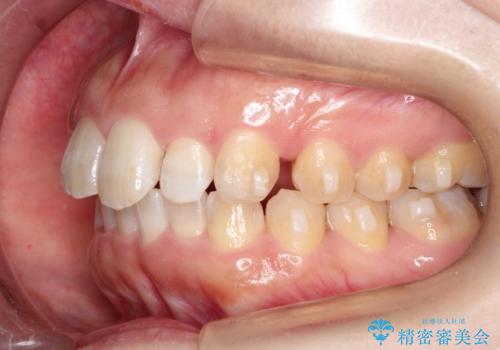

初診時の歯並びの状態としては、上の前歯が下に対して前に飛び出た上顎前突という状態で、前歯は大きく前に飛び出した状態により患者様も口の閉じづらさを感じているとのことでした。また上顎に軽度の叢生(ガタガタ)がありました。

抜歯は行わず上顎の奥のスペースを利用して歯をスライドする方法の他に歯列弓の拡大やディスキング(歯と歯の間の隙間を作る処置)を行い叢生を改善しました。